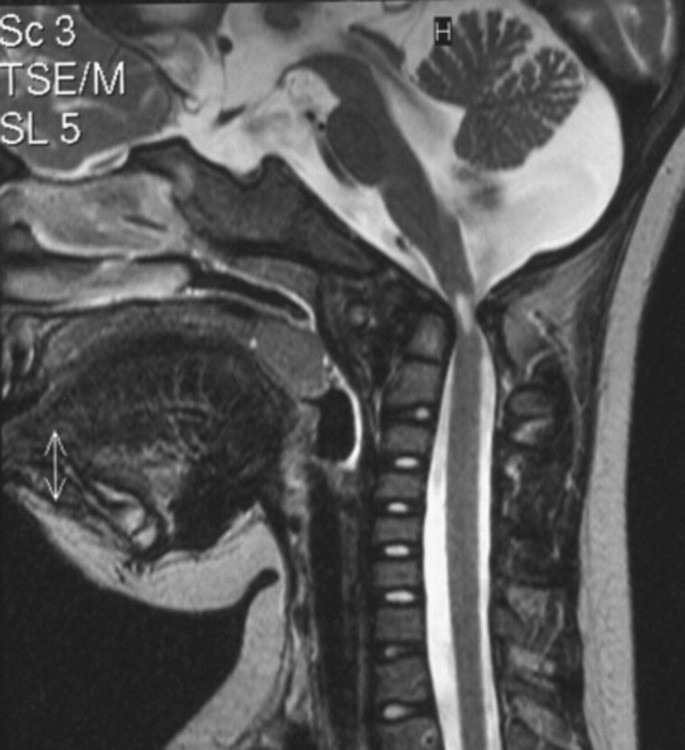

Naast de VAD bestaat ook de Internal arotid Artery Dissection _ ICAD. B Representative IF images showing hEPSCs differentiated into HYP-like cells within host monkey embryos at dpf9. Facetgewrichten kunnen net als andere. Deze prothese is technisch zo geconstrueerd dat ze de functie van de verwijderde tussenwervelschijf zoveel mogelijk overneemt en vermindering van de buigzaamheid van de. Yellow dotted line indicates ICM. Arrow indicates a TD-positive hEPSC expressing GATA4.